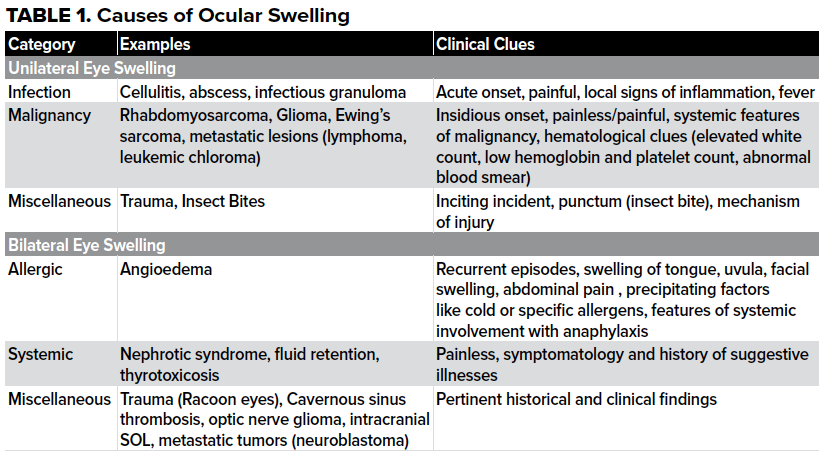

Ocular swelling (“eye swelling”) in children is a common complaint. Based on etiology and pathogenesis, they can be categorized as primary or secondary. Primary swellings arise from the globe and its orbital appendages including the orbit. Secondary swellings are ocular manifestations of a disease process originating elsewhere in the body (metastatic tumors, nephrotic syndrome etc.), see Table 1.